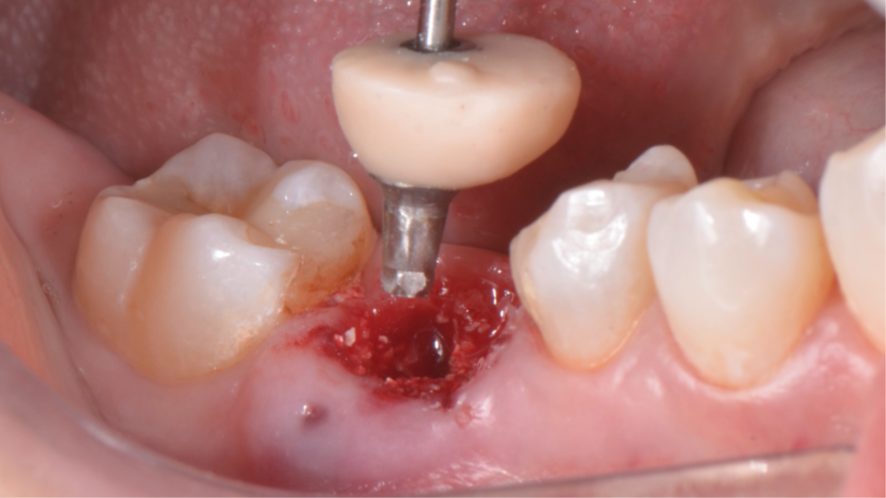

Após a instalação do implante, um cicatrizador foi colocado somente para proteger a conexão morse do implante e o GAP foi preenchido com Extra Graft 1g (Figura 7). Como foi alcançada uma alta estabilidade primária, um pilar provisório de titânio foi instalado e nele foi confeccionado um cicatrizador personalizado com resina fluida (Figuras 8, 9 e 10).